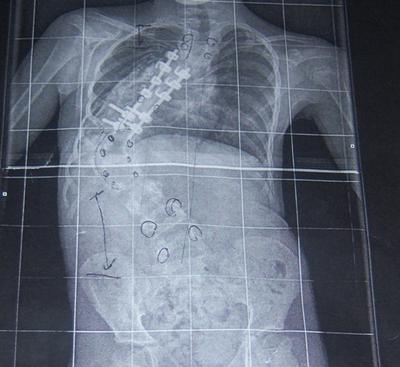

Nothing has worked and so her last surgery was to remove some of the old hardware (first pic), insert adjustable rods and to fuse most of her vertebra.

Her back, hips, rib cage etc. are still "off" and there are pulmonary issues due to the abnormal growth of her rib cage due to the scoliosis. She is restricted physically (no phys Ed, for example) and has allowances to use the elevator at school, instead of the stairs. She uses a roller backpack and has other accommodations.

I've include a couple of X-rays to give you an idea of Sam's situation. If you have any suggestions, recommendations etc. regarding chiropractic treatment for Sam I would appreciate it.

Whilst it's not conclusive, because it would appear the x-rays were taken lying down, is that Sam may have a severely short leg. Has there ever been mention of this, and is she wearing a lift in her shoe? It could make a huge difference.

You are right. A scoliosis of this nature, and the short leg causing it, in part let it be said, will have profound affect on other joints in her neck, but also in the hip and knee. These peripheral problems also need to be addressed.